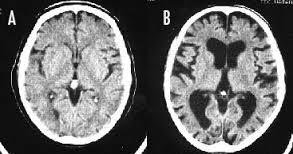

※写真は左Aが正常の脳、右Bが喫煙者の脳です。

左の脳と比べて右の脳は隙間だらけになってしまっています。

タバコを吸うと脳がすっきりするのは真っ赤な嘘だ。研究によれば喫煙者の脳では明らかに異常が起きている。認知機能も低下し、大脳皮質が元に戻るのには25年もかかる。一刻も早くタバコなど止めたほうがいい。